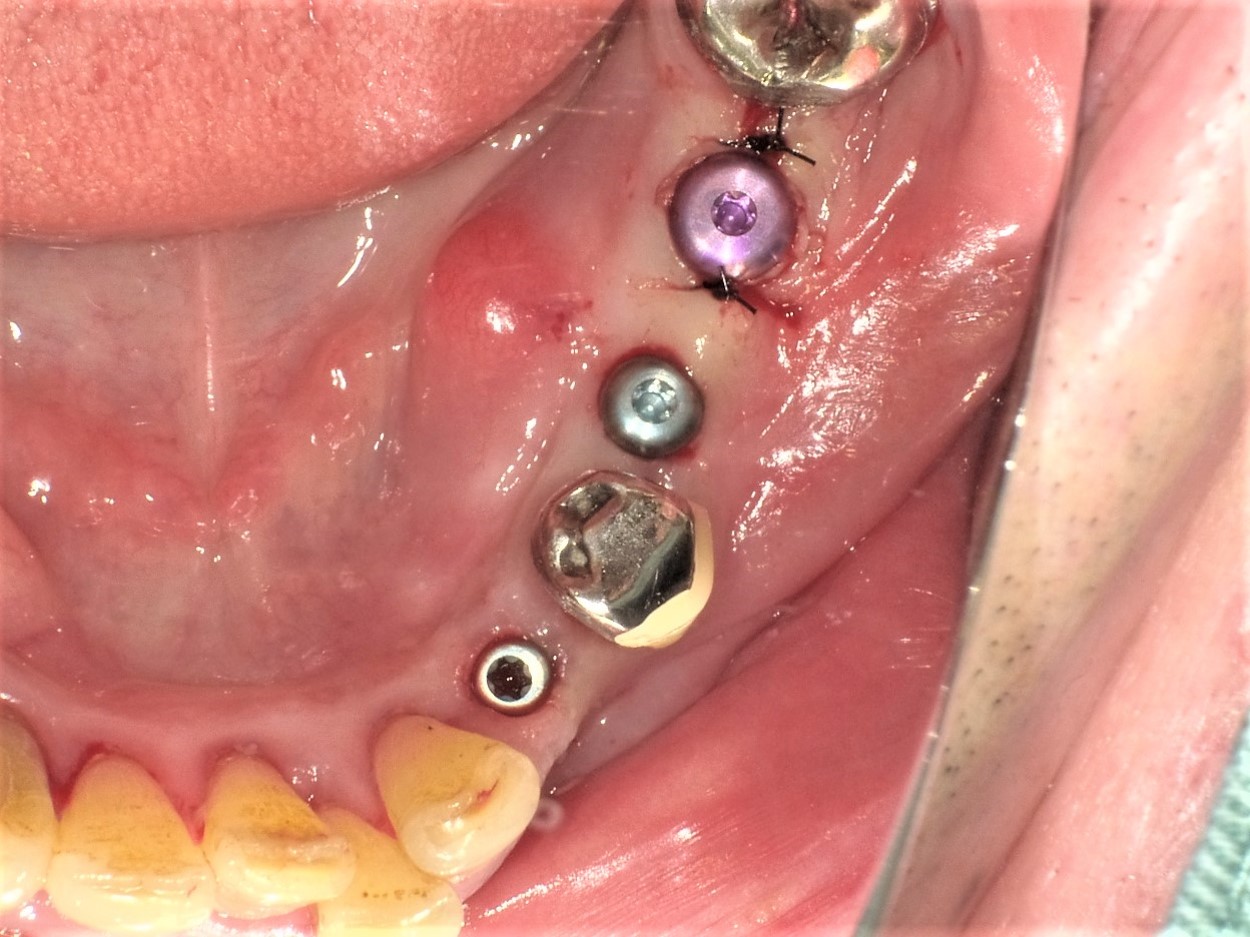

左側下顎犬歯(#33)ならびに第2小臼歯(#35)の根尖性歯周病による保存不可と第1大臼歯欠損(#36)抜歯後2か月での待機埋入症例

(50歳代 男性)

骨造成を伴う症例